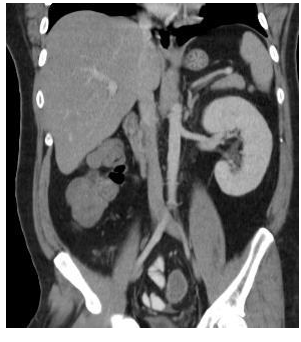

15

Q

what congenital abnormality has occured here?

A

isolated renal agenesis